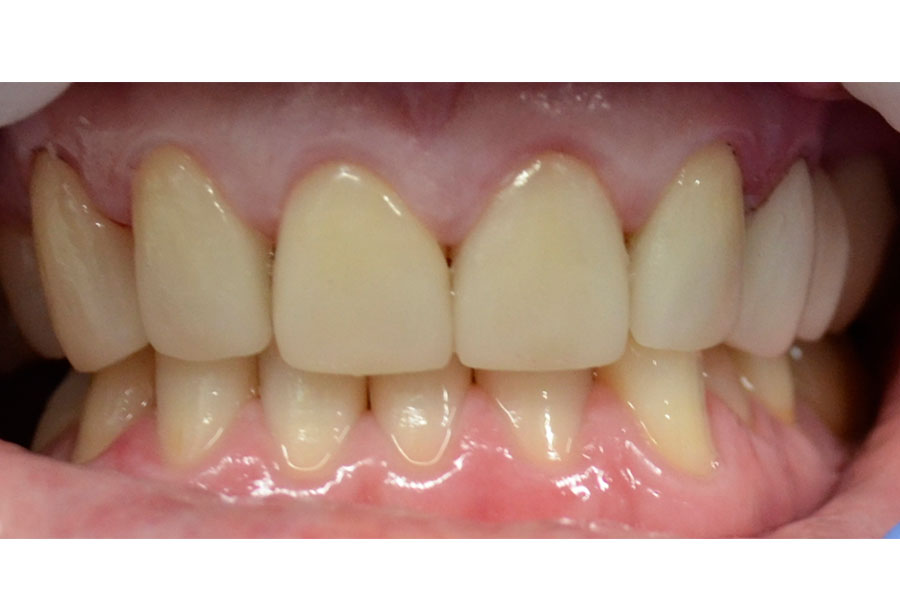

Brooke had a single crown on the upper left central incisor that had a receding gum line.

Some of the white fillings on other front teeth were also stained. Deb decided to have the crown replaced and ceramic veneers placed on other teeth. The new crown on the upper left central incisor is all ceramic (without any metal on the inside) and blends in more naturally with the veneers.